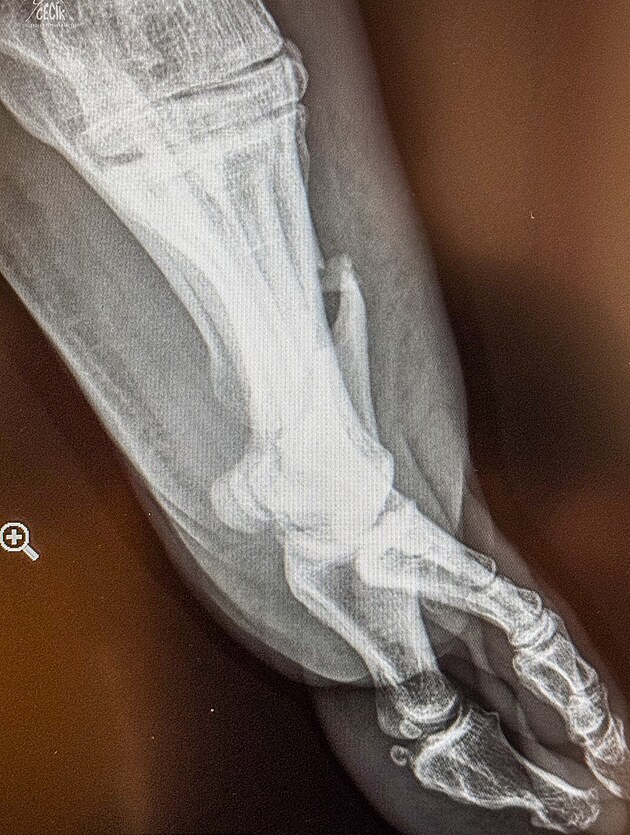

Podle jeho příspěvku na Facebooku to vypadá, že do něj najel vůz Martina Šoltyse, před kterým se podnikatel pokoušel schovat za skálu, bylo mu to nicméně málo platné. Kámen se rozlomil a vážně Cíglerovi poranil nohu.